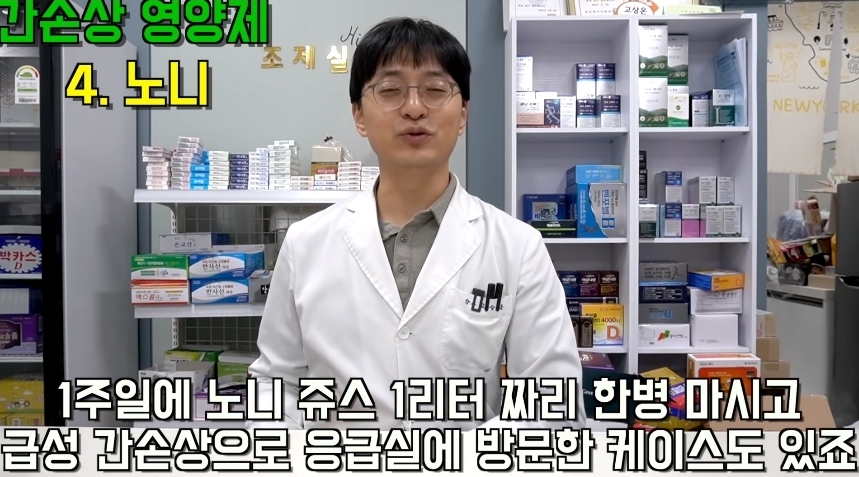

그러나 한번만 먹어도 간이 망가질 수 있다는 영양제들에 대한 글이 온라인 커뮤니티에 올라와 누리꾼들 사이에서 엄청나게 화제가 되고 있다.

해당 게시물에는 먹으면 오히려 몸에 안좋은 영양제들이 올라왔다.